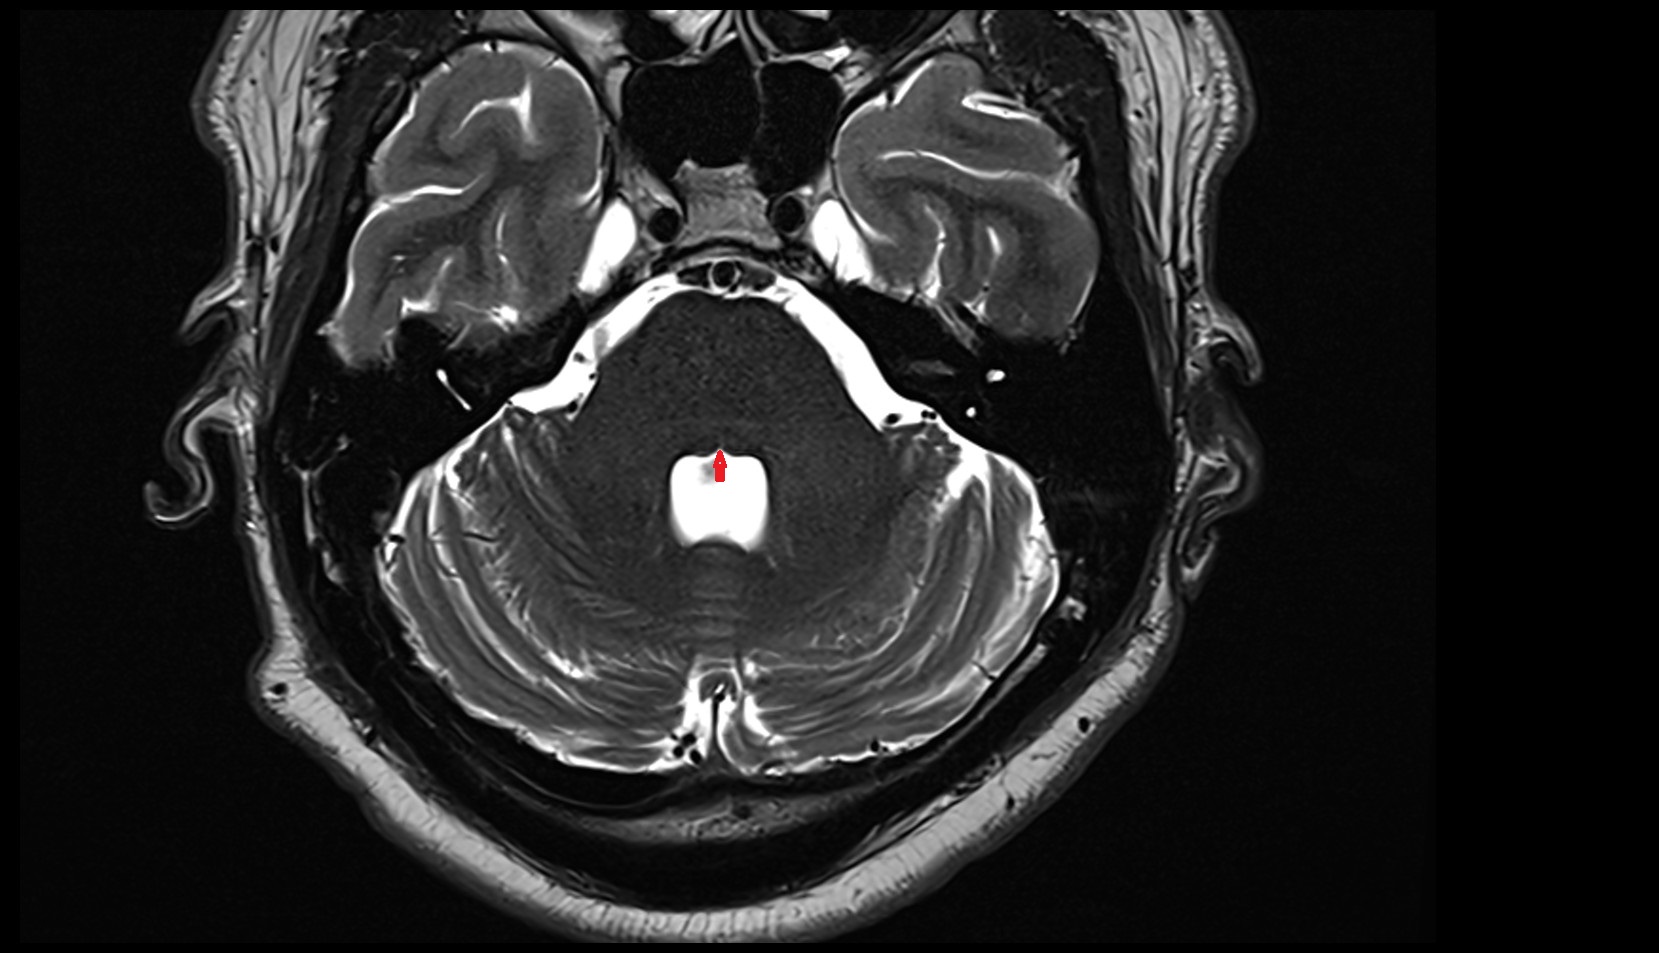

- Aqueduct of midbrain (Sylvian Aqueduct)

- Fourth ventricle

- Cerebral aqueduct